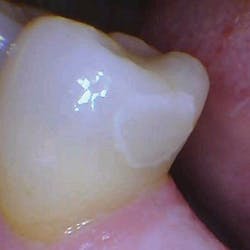

With the help of magnification, we are able to prepare small Class II lesions without sacrificing the marginal ridge, ensuring the longevity of our restoration and maximizing the remaining tooth structure with this minimally invasive approach (figures 3a–3d).

Figures 3a–3d: Minimally invasive Class II preparation with marginal ridge preservation